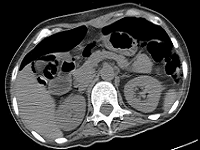

PEG tube를 처음 삽입할때(PEG tube 처음 만들때)는 공기를 최대한 주입해서 하므로 위가 복벽에 가까이 위치하지만 PEG tube를 교체할때는 위의 음식물이 없는상태이므로 위는 주먹만하게 작아진 상태입니다.

따라서 그때는 복벽과 떨어지는 경우가 매우 많습니다.

교체시 심각한 합병증(위치이탈,공기배증) 및 이로인한 감염, 복막염, 패혈증 등으로 사망위험이 있습니다.